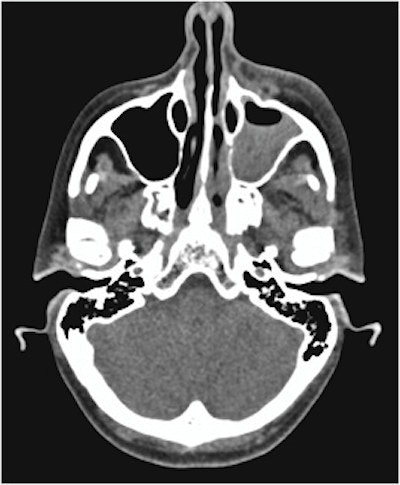

Computed tomography (CT) scans revealed swelling and fluid around the woman's eye and partial opacification of her maxillary sinus and aided in the diagnosis of the rare but deadly bacterial infection, odontogenic orbital cellulitis. Surgery treated her infection but the woman has complete vision loss in her left eye, they wrote.

CT scans showed that her sinuses had significant preseptal and postseptal swelling with retro-orbital fat stranding with small volume fluid noted at lateral and superior left orbit, with no drainable collection in the orbit. The imaging also showed partial opacification of the patient's left maxillary sinus and anterior ethmoid air cells. The scans showed that her condition met the criteria for orbital cellulitis, they wrote.